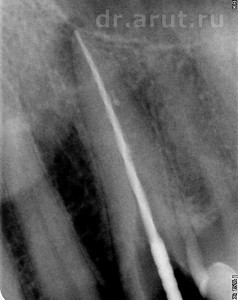

Лечение: После удаления пломбы был обнаружен титановый штифт, который после продолжительных усилий был извлечён, и благодаря этому создан доступ к корневому каналу. Во время распломбирования корневого канала по ходу пломбировочного материала (так как он является ориентиром), оказалось что канал далее непроходим. Проведя Rg-графию 23 зуба вместе с эндодонтическим инструментов выяснили, что в корне 23 зуба создан ложный канал и дальнейшая попытка его прохождения приведёт к перфорации корня. Около верхушки эндодонтического инструмента всё ещё оставалось небольшое количество пломбировочного материала, и было принято решение не продолжать распломбировывать и соответственно оставить его в ложном канале.

- Прохождение канала на всю длину